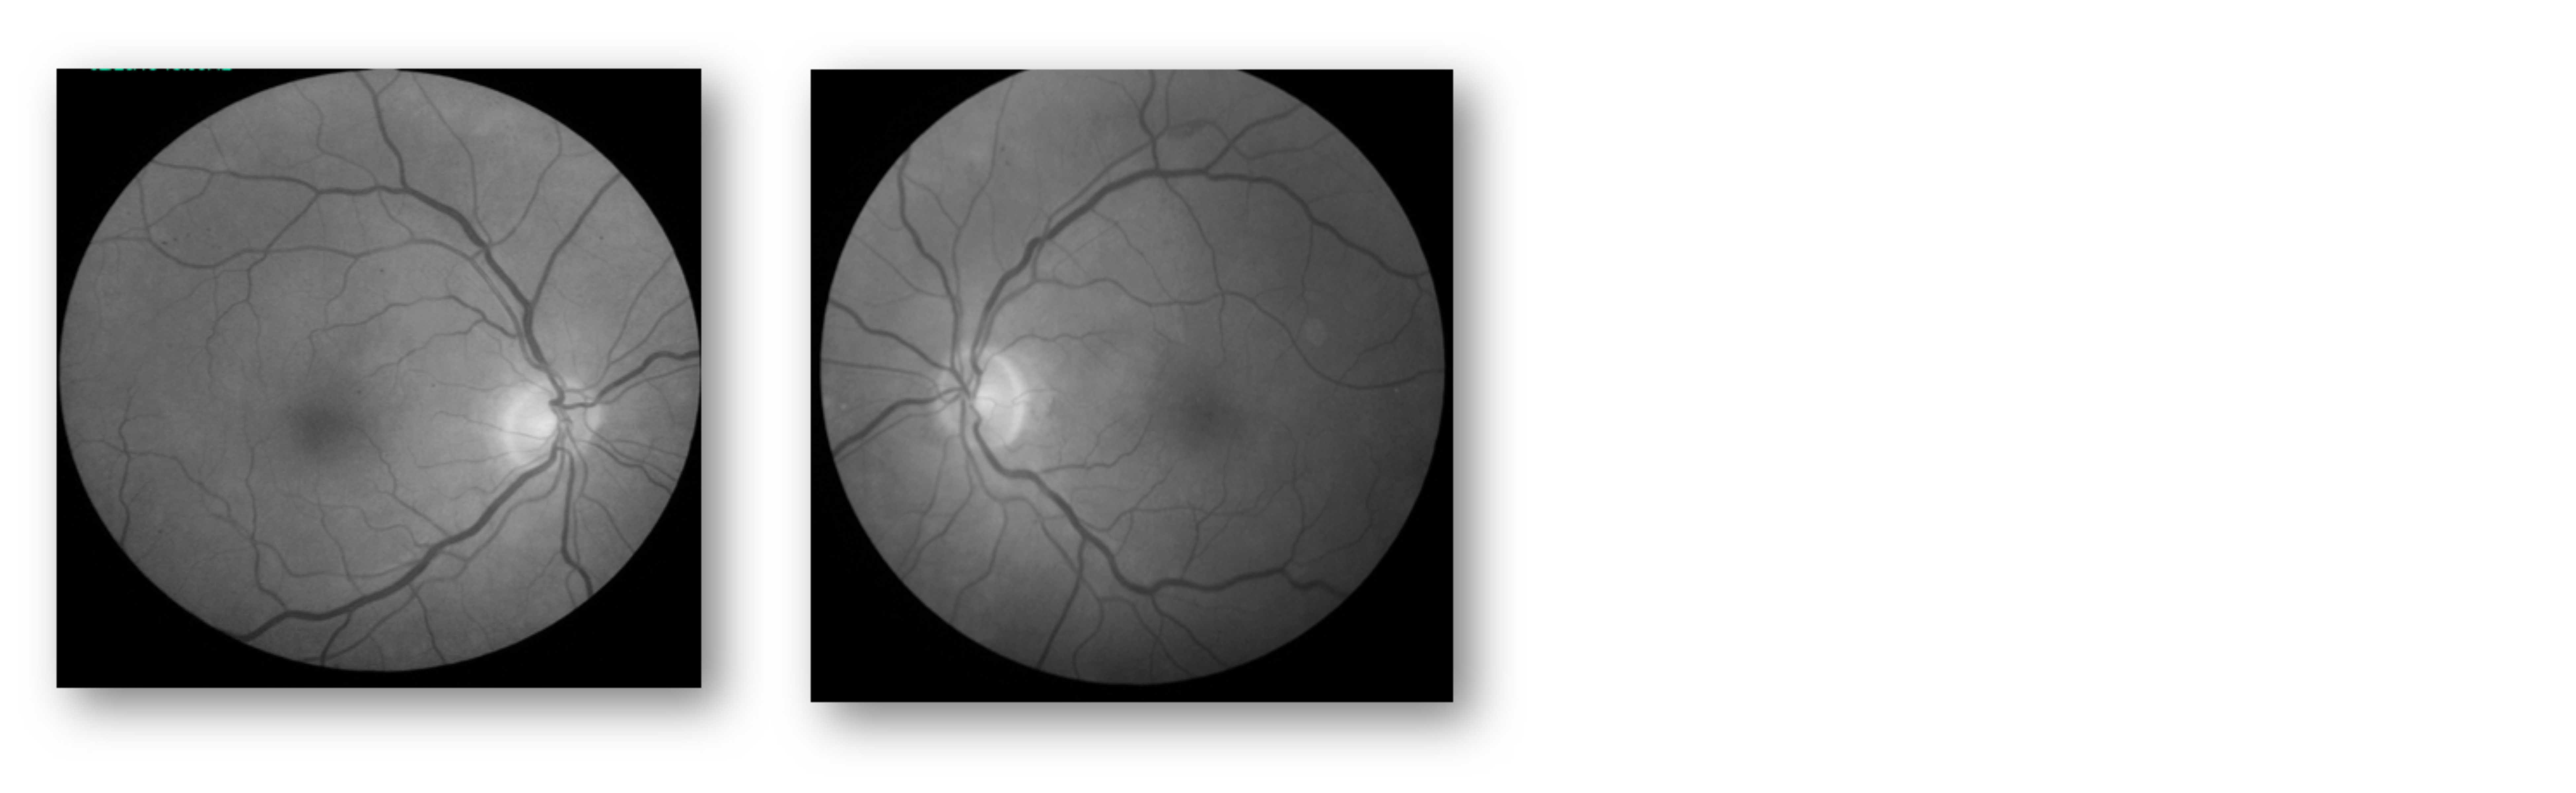

At the baseline exam, best corrected visual acuity was 20/20 OU, with normal pressures. I noted that he had mild non-proliferative diabetic retinopathy (NPDR), with a few microaneurysms that are barely evident on the fundus exam photos (Figure 1). Furthermore, the patient’s OCT looked normal (Figure 2).

Figure 1: Fundus Exam